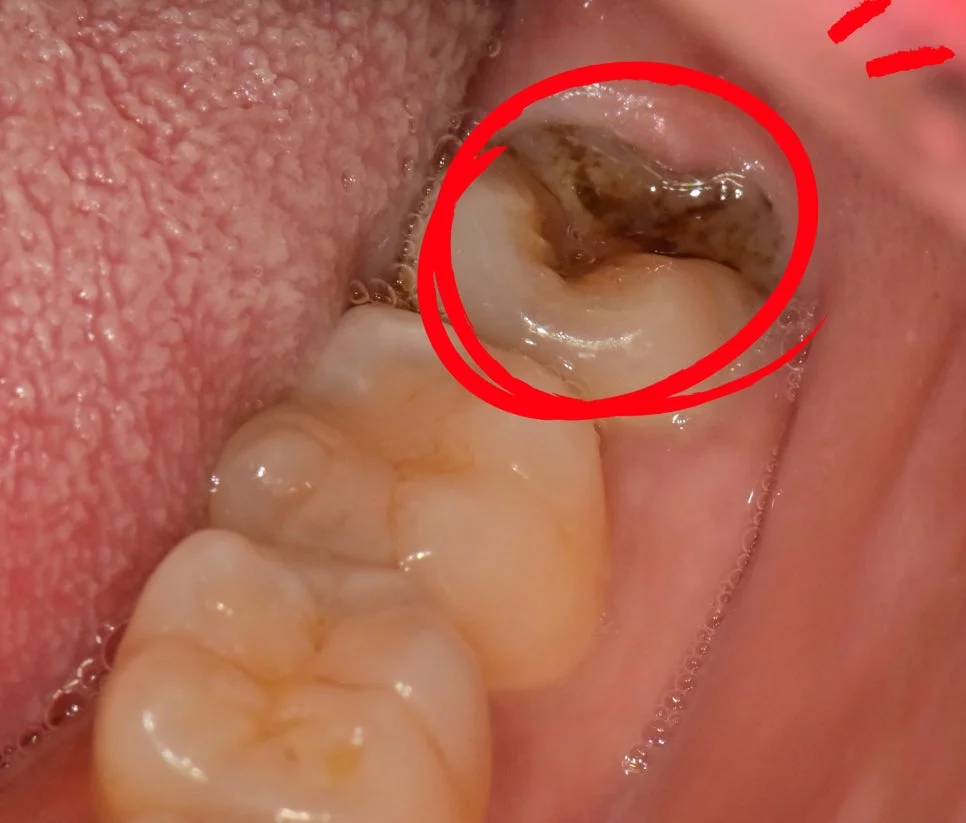

매복 사랑니 좌측 구내 잇몸 아래 매복 상태

좌측 구내 사진 (잇몸 아래 매복)

제2대구치와 사이 관리가 어려운 좌측 하악 매복 사랑니입니다. 살짝 맹출된 상태이지만 관리가 되지 않아 발치가 필요한 상태입니다.